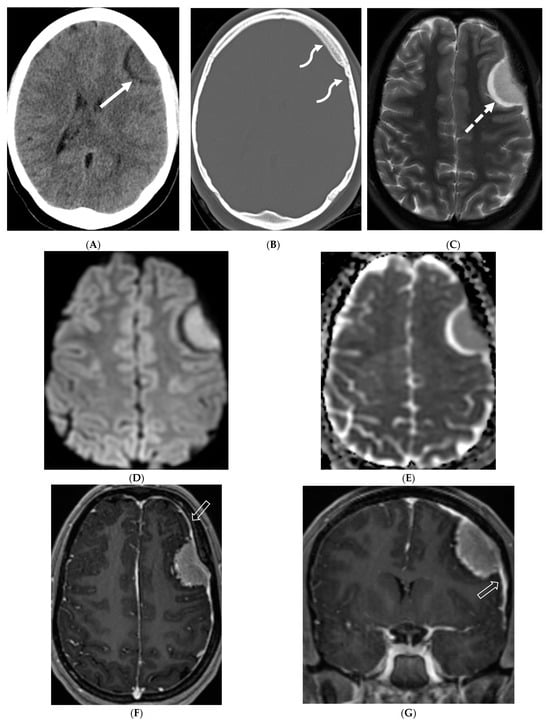

Figure 5.

Axial CT (A,B), axial T2 fat saturated (FS) (C), Axial Diffusion Weighted Imaging (DWI) & Apparent Diffusion Coefficient (ADC) (D,E), axial and coronal post contrast (F,G): 15-year-old girl with nausea and headaches. CT shows iso-dense dural-based mass in the left anterior cranial fossa (arrow). Adjacent bone is hyperostotic and has irregular cortex (curved arrow). The lesion is isointense with cortex, which is buckled inwards from the mass. A hyperintense rim surrounds the mass representing CSF cleft (dashed arrow). No significant restricted diffusion is noted. The mass enhances intensely and uniformly. A dural tail (open arrow) of benign, nonneoplastic reactive thickening is present adjacent to the left frontal mass, characteristic of classic “typical” WHO grade 1 meningioma.